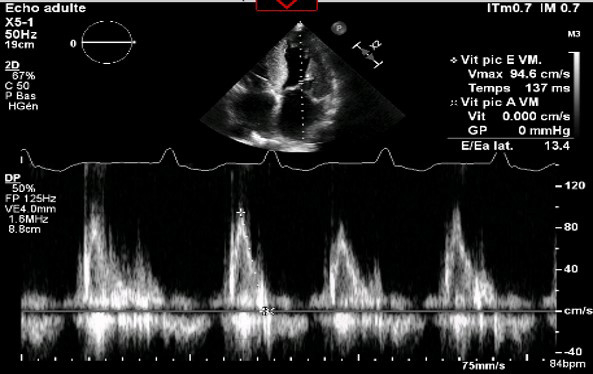

Figure 3 : Mesure du flux transmitral au doppler pulsé (évaluation PRVG)

- Pressions de remplissage VG probablement élevées